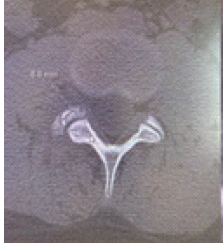

Unusual Presentation of Spinal Osteoid Osteoma: A Case Report

Mehmet Erkilinc

………………………………p.86-89